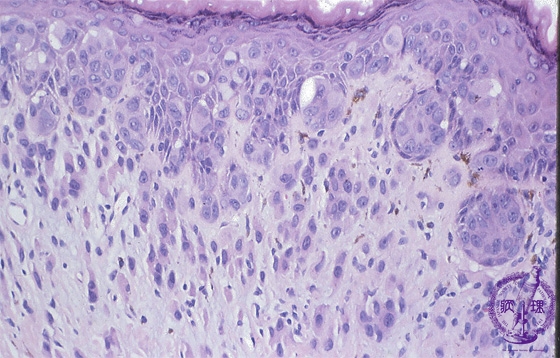

• (9)Extramammary Pagetfs disease

Microscopic findings: Paget cells spread within the epidermis and epithelium of the sweat ducts. Some Paget cells also invade the dermis.